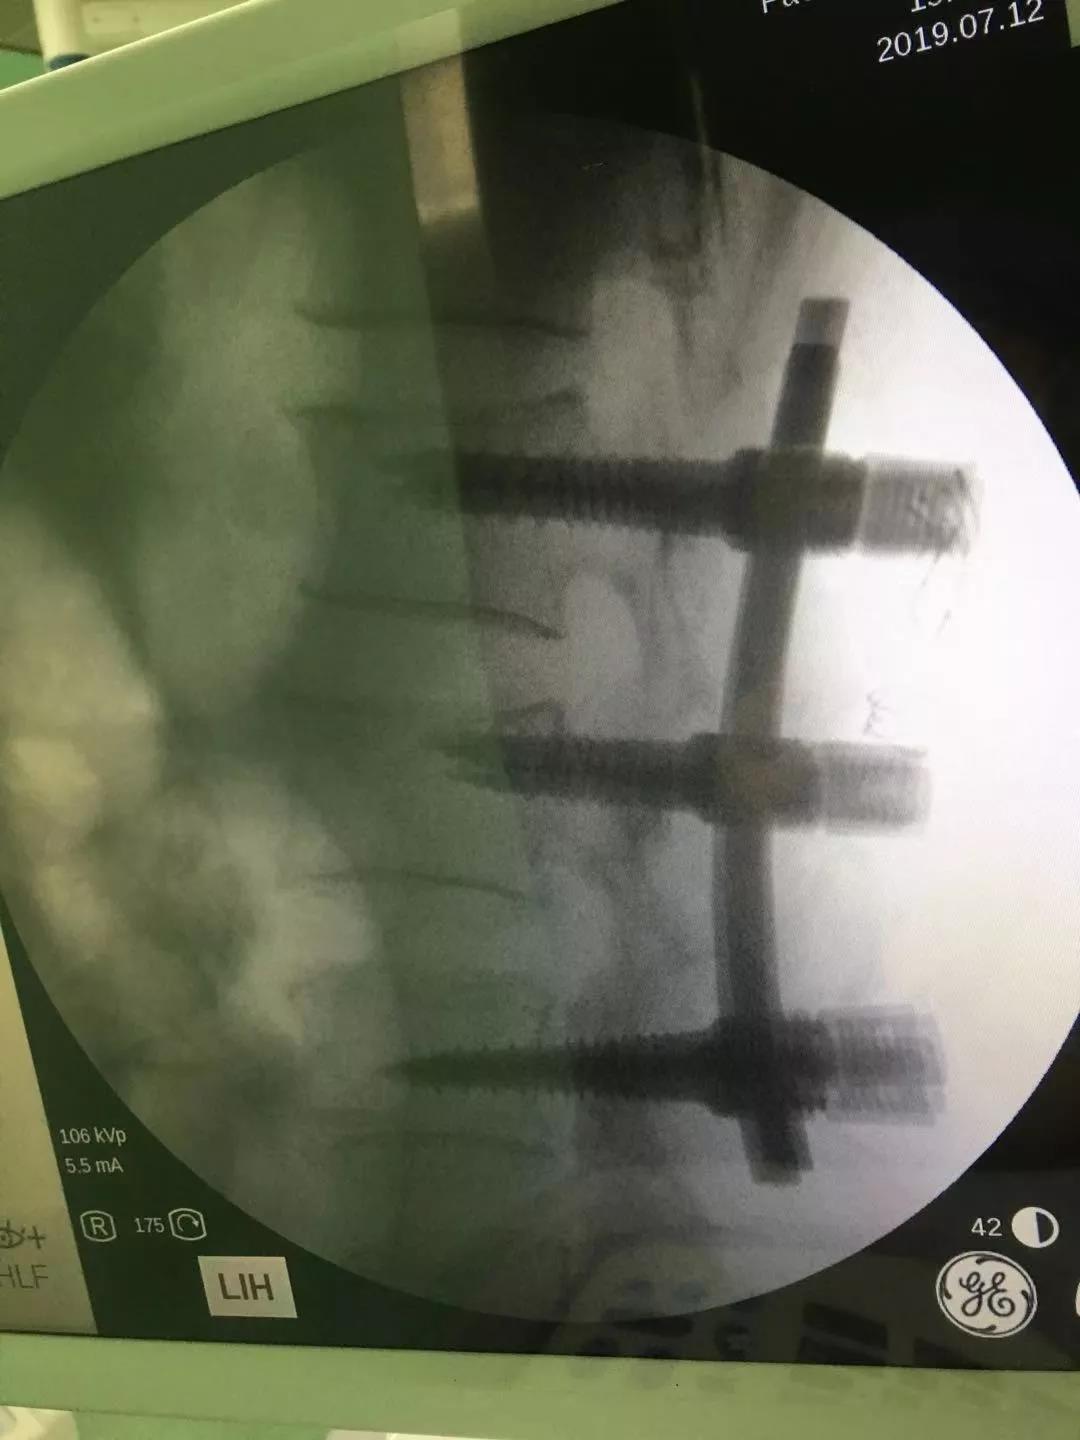

入院后完善术前检查,急诊在全麻下行“后路切开,T12椎体爆裂骨折复位,T11、T12、L1、L2钉棒系统内固定,T12左侧部分椎板切除椎管开窗减压术。

术后预防感染、消肿镇痛、营养神经、指导卧床活动锻炼等对症支持治疗,复查DR及CT示椎体高度恢复,椎管减压充分。

这张表达得更清晰些,这是术前压缩1/2的,椎管内也有骨块占位的。

这个病例要我选择的话,我很欣赏傅教授最后提供的那一张照片,就是在病椎的上下各打一对钉子,然后在病椎打一对短钉,短钉穿过椎弓根就可以,傅主任刚才也提到他在2005年就做过相关临床研究,短钉可以帮助复位和维持,有一定好处,我认为有一定道理。